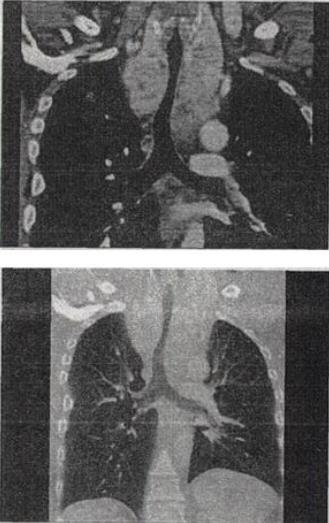

- 单项选择题 患者男,67岁,呼吸困难半年余,结合影像学检查,最可能的诊断是()。

A、胸骨后甲状腺肿

B、淋巴瘤

C、间皮囊肿

D、纵隔畸胎瘤

E、胸腺瘤

- A